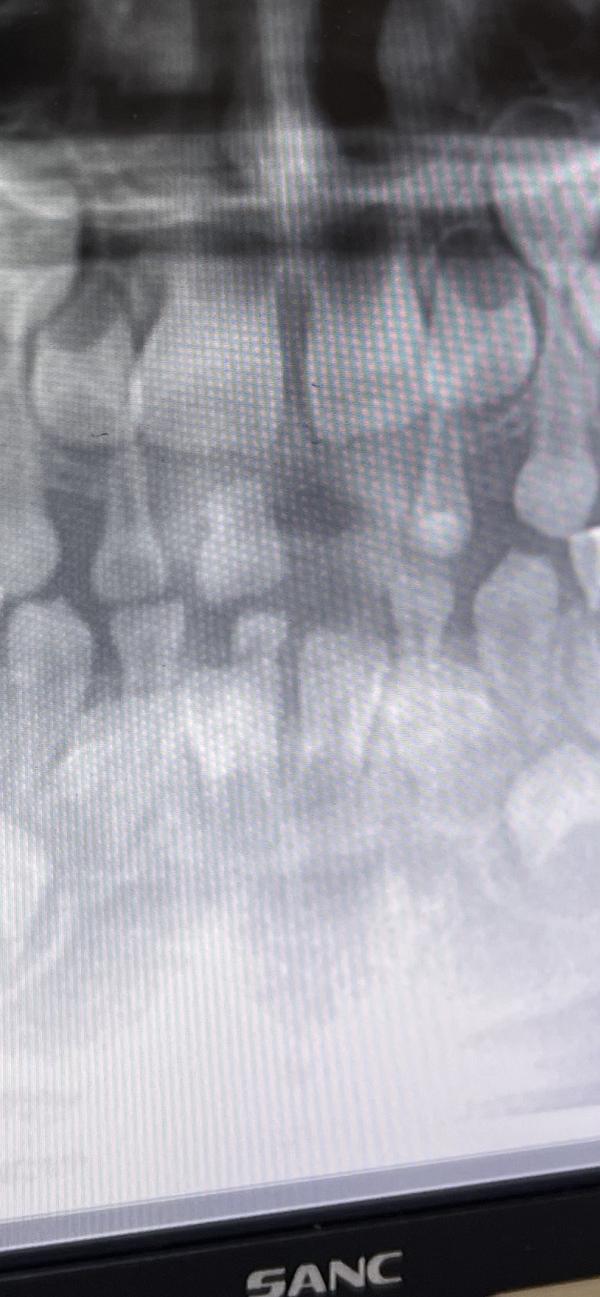

Вчера делали рентген. Пару месяцев назад выпал нижний зуб. Сегодня выпал второй нижний. Оба были без корня.

Девочки, подскажите пожалуйста это же обычная смена зубов? У второго верхнего резца тоже корень начал рассасываться? (Первый верхний потерял когда ударился и сломал корень)

Как вы считаете здесь по рентгену идёт смена зубов? У меня у дочек менялись позже и когда выпадал молочный был уже виден постоянный, т.е. постоянные буквально выталкивали молочные. А у сына первый выпал пару месяцев назад, а нового зуба и не видно

На снимке зуб есть, уже хорошо